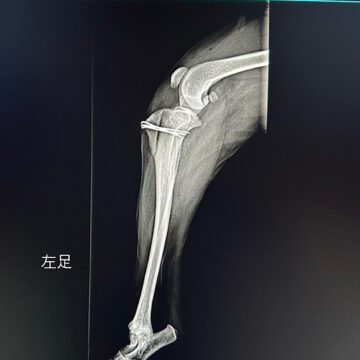

お願い 2024.09.10 パテラ(膝蓋骨脱臼)グレード3の手術を終えました ▶︎ 続きはブログへ 毛呂山ブリーダー事件で保護されたトイプードル系の女の子3頭を、当会で迎えることになりました。 そのうち1頭は、後ろ足を引きずるような歩き方や、膝を曲げて腰を落としたような姿勢で歩くなど、歩行に異常が見られていました。動物病院での診察の結果、パテラ(膝蓋骨脱臼)でグレード3であることが判明し、緊急手術いたしました。 皆様からの手術費への温かいご支援を心よりお願い申し上げます。 あかねちゃんの詳細はこちら 2023.04.14 2026.02.13 あかねちゃん(募集停止中) 里親選考中のため募集停止中です (キャンセル待ちは受付中) 【名前】あかねちゃん 女の子♀ 【推定誕生日】 2019年8月28日() 【犬種】トイプードル 【体重】約5.5kg 見学希望の方はこちら... 里親選考中のため募集停止中です (キャンセル待ちは受付中) 【名前】あかねちゃん 女の子♀ 【推定誕生日】 2019年8月28日() 【犬種】トイプードル 【体重】約5.5kg 見学希望の方はこちら... Post ブリーダー事件で保護されたプードルちゃんたちへご支援のお願い 前の記事 ボランティア募集再開のお知らせ! 次の記事